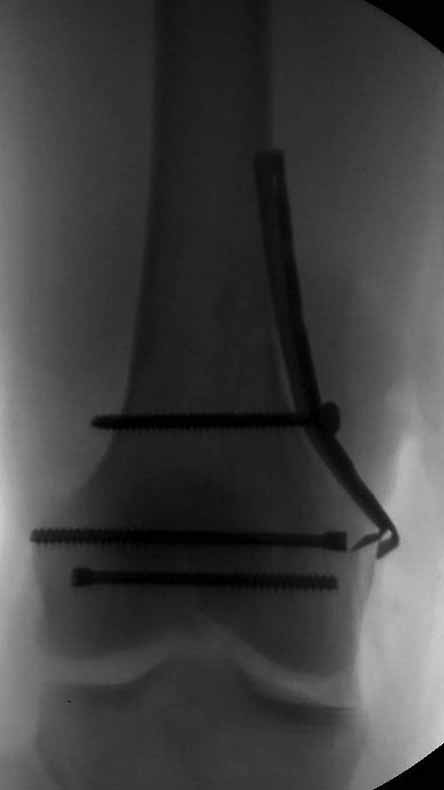

И уже лет шесть мы используем возможность ввести в дистальное овальное отверстие 3 винта, которые именно запираются в этом отверстии, не люфтят, а обеспечивают угловую стабильность - см картинку.

Получается и стабильно, и очень дистально, нижний край отверстия в 3 мм от дистального конца гвоздя.

С моей точки зрения, безусловная ценность предложенного Вами, Александр Николаевич, стержня состоит в возможности введения блокирующих винтов максимально близко к суставной поверхности дистального отломка, что значительно расширяет показания для применения интерлокинга. Можно предположить, что в техническом плане таким образом ввести блокирующие винты является непростой задачей. Кроме того, все они расположены в одной плоскости на небольшом расстоянии друг от друга.

Мне представляется, что конструкция с максимальными прочностными характеристиками будет иметь вид предложенной во вложенном файле. Такую конфигурацию расположения блокирующих отверстий на дистальном конце имеет стержень для большеберцовой кости фирмы ChM. Для бедренной кости такой стержень мне неизвестен. Поэтому в необходимых случаях (хорошо, что такие случаи встречаются не часто), как вариант, мы используем custom made стержень.